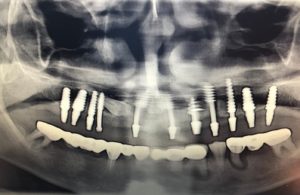

implanturi rapide bacau (3)